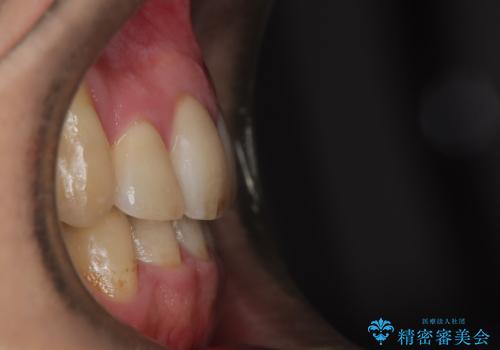

ガタガタの歯並び、八重歯をなおしたい、骨格性下顎前突 カモフラージュ矯正

- 前歯のガタガタと八重歯を治したいということで矯正を希望された患者様です。

骨格的に上顎骨が小さいために相対的に下顎骨が前に出ていたため、歯の傾きなど理想的な仕上がりが難しく、外科矯正ではなく歯列矯正の場合はカモフラージュ矯正になること説明の上、矯正治療を進めることになりました。

上顎は左右5番抜歯、下顎は左右4番抜歯しています。

八重歯(3番)などは歯肉移植も検討できればよいかなと思います。